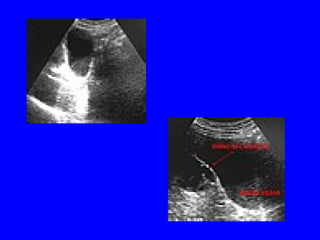

Ecografía (Urgencias): vesicula biliar

Conclusión: ABSCESO HEPÁTICO

SECUNDARIO A PERFORACIÓN

VESICULAR EN EL CURSO DE UNA

COLECISTITIS AGUDA

Hb 14.1 Hto. 40% Plaquetas106.000 Leucos 5.200 Glucosa 123 Función renal y hepática normal. Amilasas normales. PCR 19.3 VSG 96 Serología VIH, Salmonella, Brucela,LUES, Leismania, Ameba e hidatidosis, Negativas Rx Torax: sin evidencia de infiltrados Ecografía (Urgencias): vesicula biliar distendida

Conclusión: ABSCESO HEPÁTICO SECUNDARIOA PERFORACIÓN VESICULAR EN EL CURSO DE UNA COLECISTITIS AGUDA